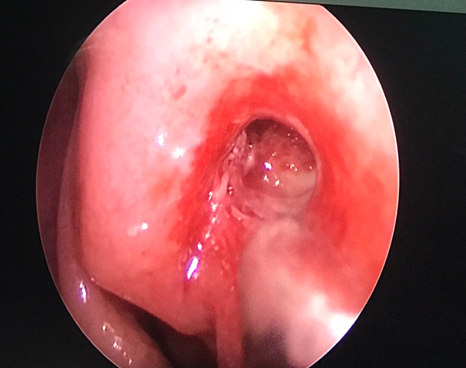

Vừa qua khoa Mắt - Bệnh viện Đa khoa tỉnh vừa tiếp nhận vầ điều trị Bệnh nhân nữ 49 tuổi vào viện vì xuất hiện khối sưng nề góc trong mắt trái kết hợp chảy mủ và chảy nước mắt nhiều. Tại đây bệnh nhân được xác định chẩn đoán Mắt trái: Viêm mủ túi lệ/ Tắc lệ đạo, bệnh nhân đã được điều trị nội khoa tích cực, triệu chứng lâm sàng giảm dần. Khoa Mắt và khoa Tai mũi họng đã kết hợp phẫu thuật cho bệnh nhân bằng phương pháp Nối thông túi lệ mũi bằng nội soi. Phẫu thuật này đã tạo đường thông trực tiếp từ túi lệ sang khoang mũi nhằm dẫn nước mắt từ mắt sang mũi. Sau phẫu thuật 2 ngày, các triệu chứng lâm sàng của bệnh nhân thuyên giảm và được ra viện sớm.

Hình 1. Xác định vị trí phẫu thuật